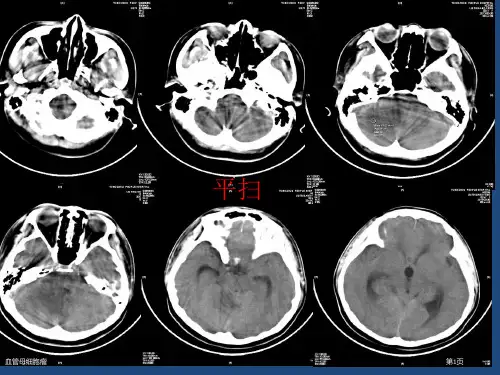

脑血管母细胞瘤CT和MRI特征:囊腔型脑血管母细胞瘤特征性表现是囊腔大,结节小及结节显著异常强化,影像学诊断囊性血管母细胞瘤的关键是检出肿瘤壁结节。

肿瘤壁结节大多单个、突入囊腔内,少数有多个壁结节或结节在瘤周。

多数囊壁无强化,少数囊壁有胶质增生或有肿瘤组织时可发生强化。

实质性脑血管母细胞瘤的影像表现没有囊结节典型,诊断困难。

因肿瘤由致密毛细血管网组成,T2呈高信号,且随TE延长信号进一步增强,增强扫描呈不均质显著强化。